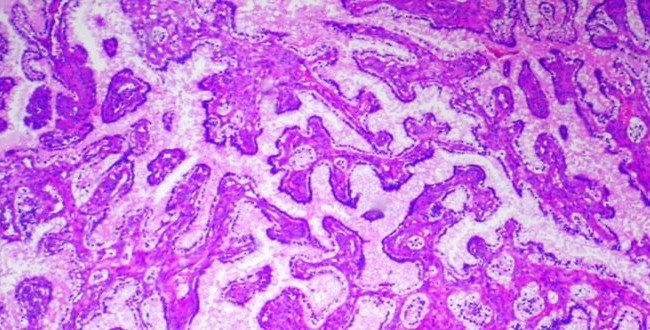

Carcinoma papilar renal de células claras

Autores: Dr. Boris Elsner, Centro de Patología, C.A.B.A. Reseña: El carcinoma papilar renal de células claras (CPRCC) forma parte del grupo de tumores renales que han sido...